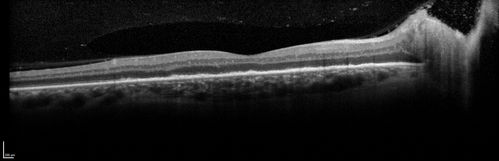

Syphillitic Optic Neuropathy and Maculopathy

46 year old woman with 2 weeks of vision loss OD.  VA 20/200 OD; 20/20 OS.  there are posterior vitreous cells on OCT in both eyes.  ICG, FAF, and FA show an abnormal macula OD.  VA improved to 20/30 within a month with treatment with PCN.